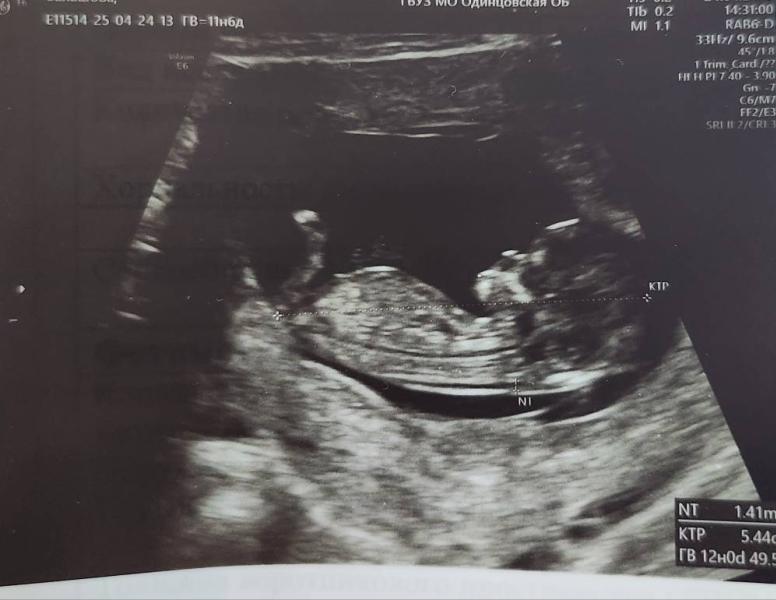

Кто у нас будет? Угадайте по первому фото!

Если судить по первому фото, кто же будет у нас? 😃

Не вижу на этом снимке половой бугорок

А я что-то не вижу бугорка, это же ноги🤔

Да, ноги

Я вижу только ноги

Вот да, ногами перегорожено и не понятно ((

Я судя по схеме вижу мальчика

Мальчик

Вижу мальчика